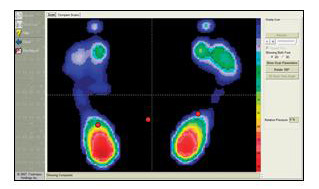

Click on the Button below for information on our new state of the art orthotic technology by Footmaxx.